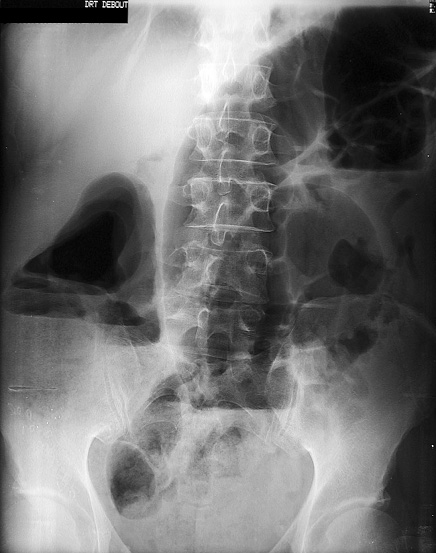

Vous disposez d'une radiographie de

l'abdomen sans préparation (photo 1).

Comment définissez-vous le syndrome que

présente ce patient ? Quels sont les

arguments cliniques et radiologiques qui

permettent de le justifier ?